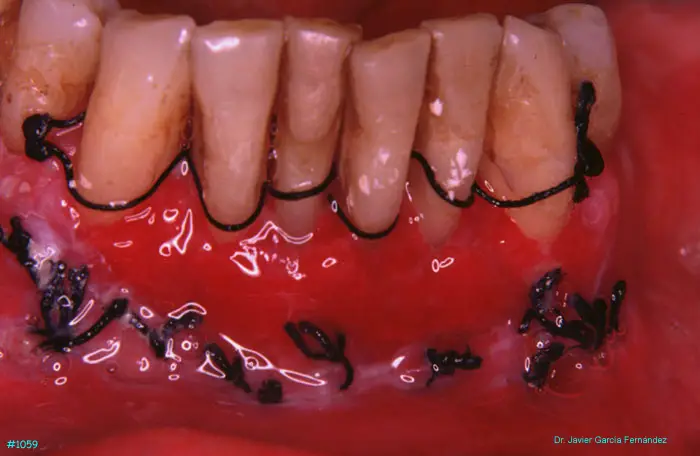

Atlas of Surgical Techniques in Periodontics. Chapter III. Atlas de Técnicas Quirúrgicas en Periodoncia